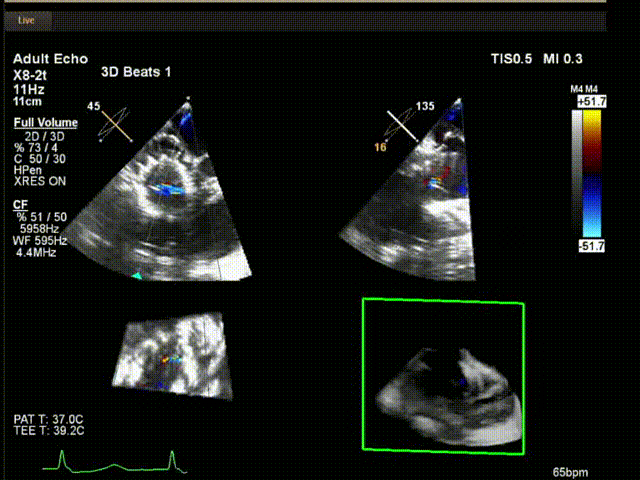

術(shù)中超聲

陸方林教授通過遠(yuǎn)程線上帶教的方式,與林逸賢教授團(tuán)隊共同完成了此次LuX-Valve Plus人工瓣膜的首例植入。術(shù)后食道超聲提示三尖瓣反流完全消失,無瓣周漏,且LuX-Valve Plus人工瓣膜的兩個夾持鍵成功抓取瓣葉,錨定牢固,人工瓣膜穩(wěn)定性良好。